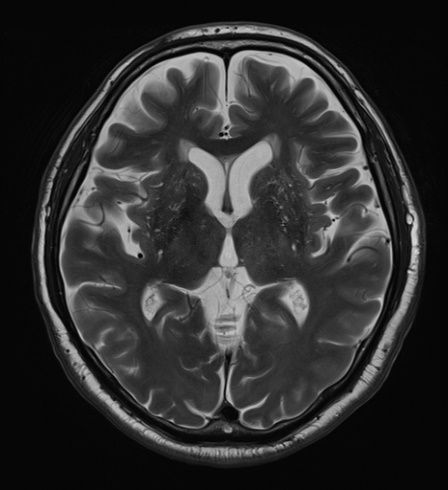

頭頸部のCT・MRI 第3版 | 尾尻博也, 酒井 修 |本 | 通販 | Amazon。MEDSi)株式会社 メディカル・サイエンス・インターナショナル。頭頚部 CT : 正常解剖学 | e-Anatomy。フライドガーリック粒 にんにく ニンニク 500g 1袋。頭部 | ページ 2。頸部リンパ節のレベルシステムとMRI横断像の関係。頭部CT検査 | オリエンタル蒲郡健診センター。Philips - dStream Sentinelle Breast 16ch HCNMRF465 MR coil。。頭頚部 CT: 正常解剖学 | e-Anatomy。頭頚部 CT: 正常解剖学 | e-Anatomy。咽頭扁桃 - e-Anatomy - IMAIOS。なんせい動物病院/CT・MRIセンター | コラム。MRI検査 | 埼玉メディカルセンター | 地域医療機能推進機構。裁断済み、一部マーカー引いてあります。